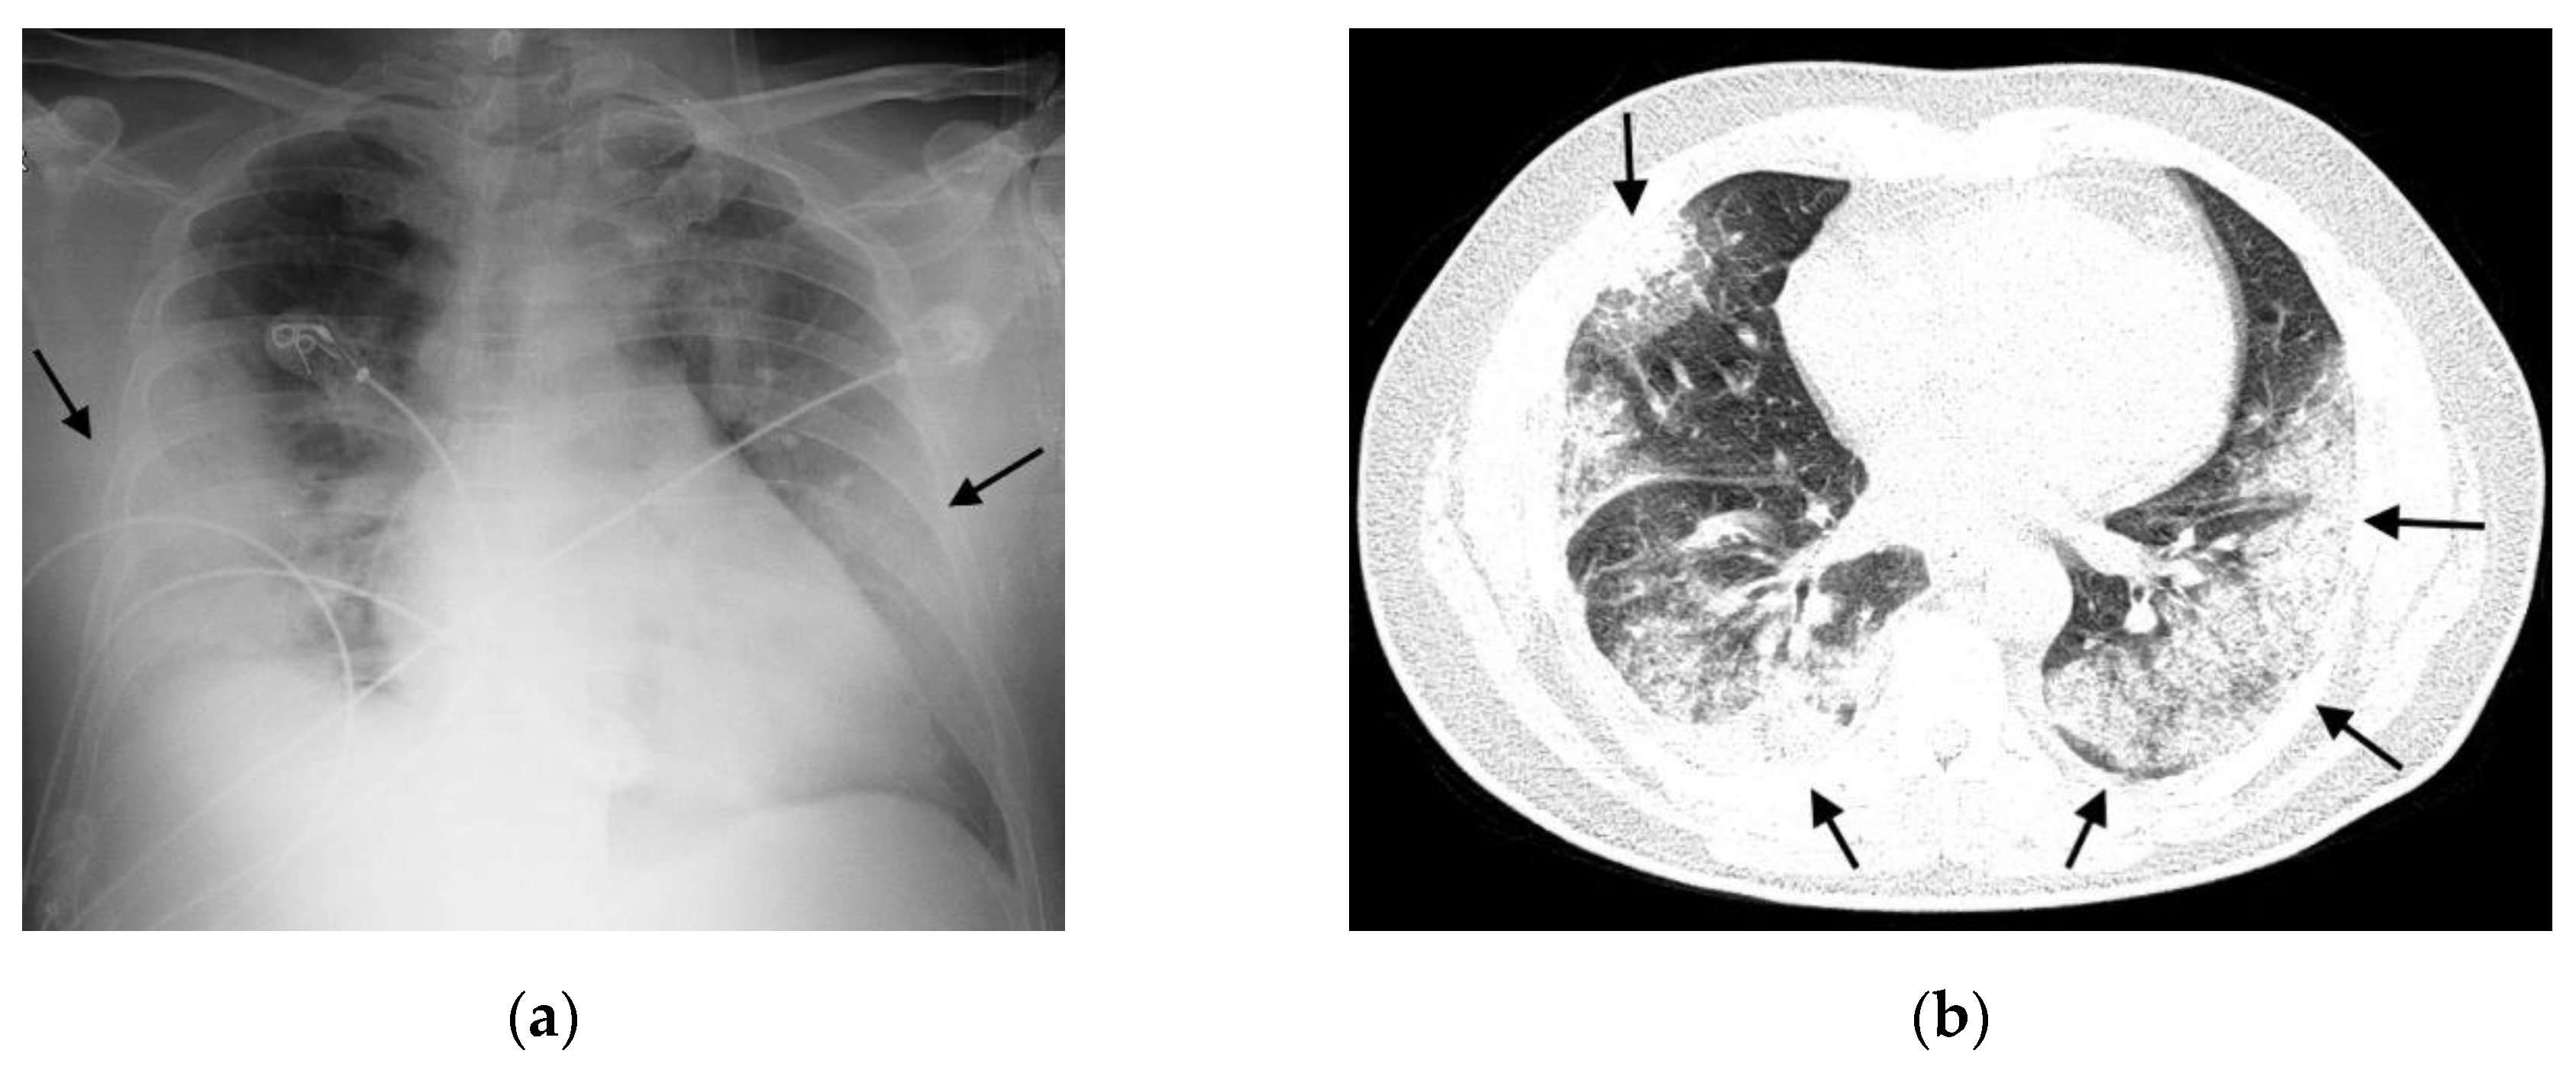

- Typical: Multifocal peripheral or central areas without a clear definition of vascular structure contours (opacity type 1) or a significant and variable increase in parenchymal density with a hazy appearance (opacity type 2); consolidations (opacity type 3) may be present but are associated with one of the other opacities.

- Possible: Opacities without a multifocal pattern or opacities type 1 and 2 in only one lobe or the upper thirds of the lungs.

- Atypical: Absence of typical or possible patterns, along with the presence of one or more of the following findings: cavities or isolated lobar/segmental consolidation (resembling bacterial pneumonia); micronodules; signs of pulmonary congestion and pleural effusions; or extensive pleural effusions.

- Negative: No findings indicative of pulmonary diseases.